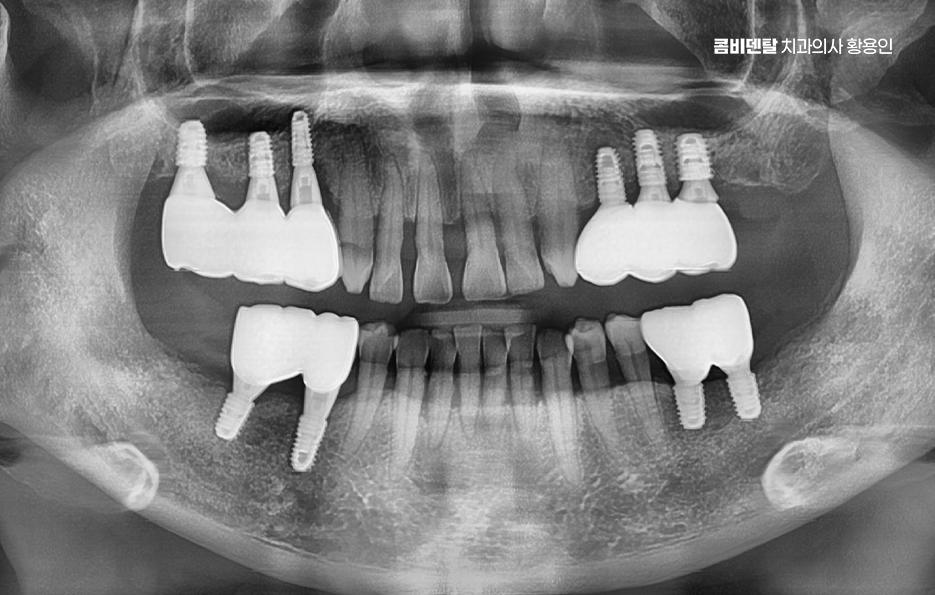

그렇다면 어금니 발치 후, 임플란트를 잘 받기 위한 방법은 뭐냐 하면 첫 번째는 시기를 놓치지 않는 것인데 발치 후 3개월 내에는 임플란트를 심는 게 이상적이며 사실 요즘은 경우에 따라 ‘즉시 식립’이라고 해서 발치 당일에 임플란트를 심는 경우도 많아지고 있기 때문에 발치와 함께 임플란트 치료 계획을 세우는 것이 이상적이라 할 수 있어요

나에게 맞는 치료를 하기 위해서는 정확한 진단과 설계가 중요하며 CT 촬영 등을 통해 신경 위치, 뼈의 양, 두께 등을 정밀하게 진단한 다음, 교합과 치열 구조에 맞는 위치에 임플란트를 심는 게 중요한데 잘못된 위치에 심어지면 오래 쓰기 어렵고, 나중에 통증이나 염증이 생길 수 있었어요.

임플란트는 처음 수술보다 이후 관리가 더 중요하다고 할 정도니까, 처음부터 잘 설계된 치료계획 아래 수술을 받는 게 중요하며 그 이후로도 사후관리를 잘하는 것이 곧 임플란트의 수명 유지에 중요한 거예요